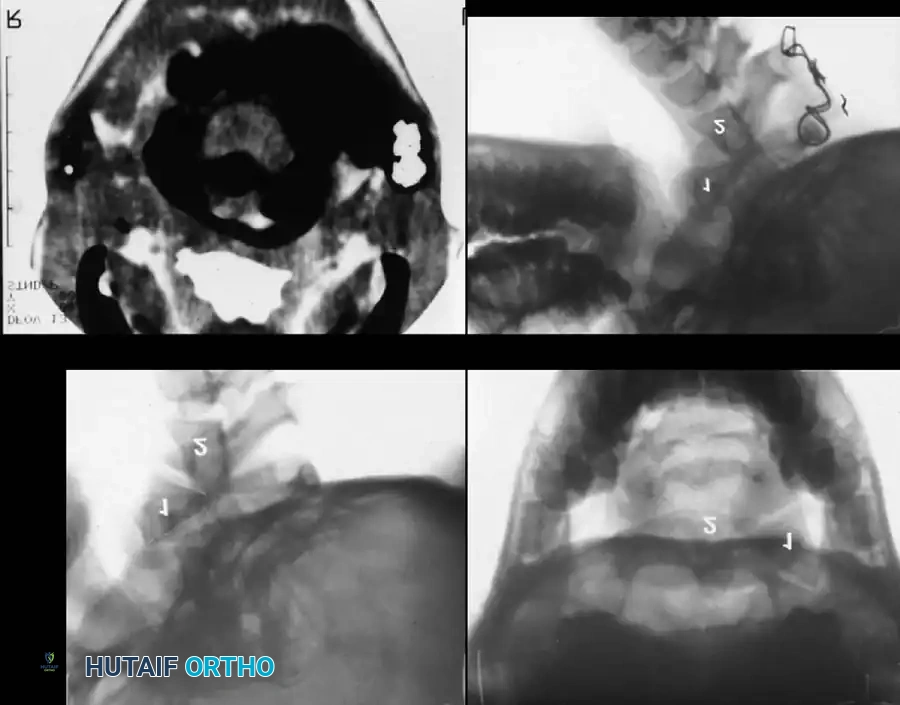

Fig. 37-33 Atlantoaxial rotatory fixation. A, Lateral radiograph shows wedge-shaped mass anterior to odontoid. B, Open-mouth odontoid view. C, CT scan. D, After C1-2 in situ fusion.

Fig. 37-34 Drawing of Wackenheim clivus-canal line. This line is drawn along the clivus into the cervical spinal canal and should pass just posterior to the tip of the odontoid.

Fig. 37-35 Method of measuring atlantooccipital instability according to Wiesel and Rothman. Translation should be no more than 1 mm.

Fig. 37-36 Powers ratio. A ratio greater than 1 is diagnostic of anterior atlantooccipital translation, and a ratio less than 0.55 is diagnostic of posterior translation.